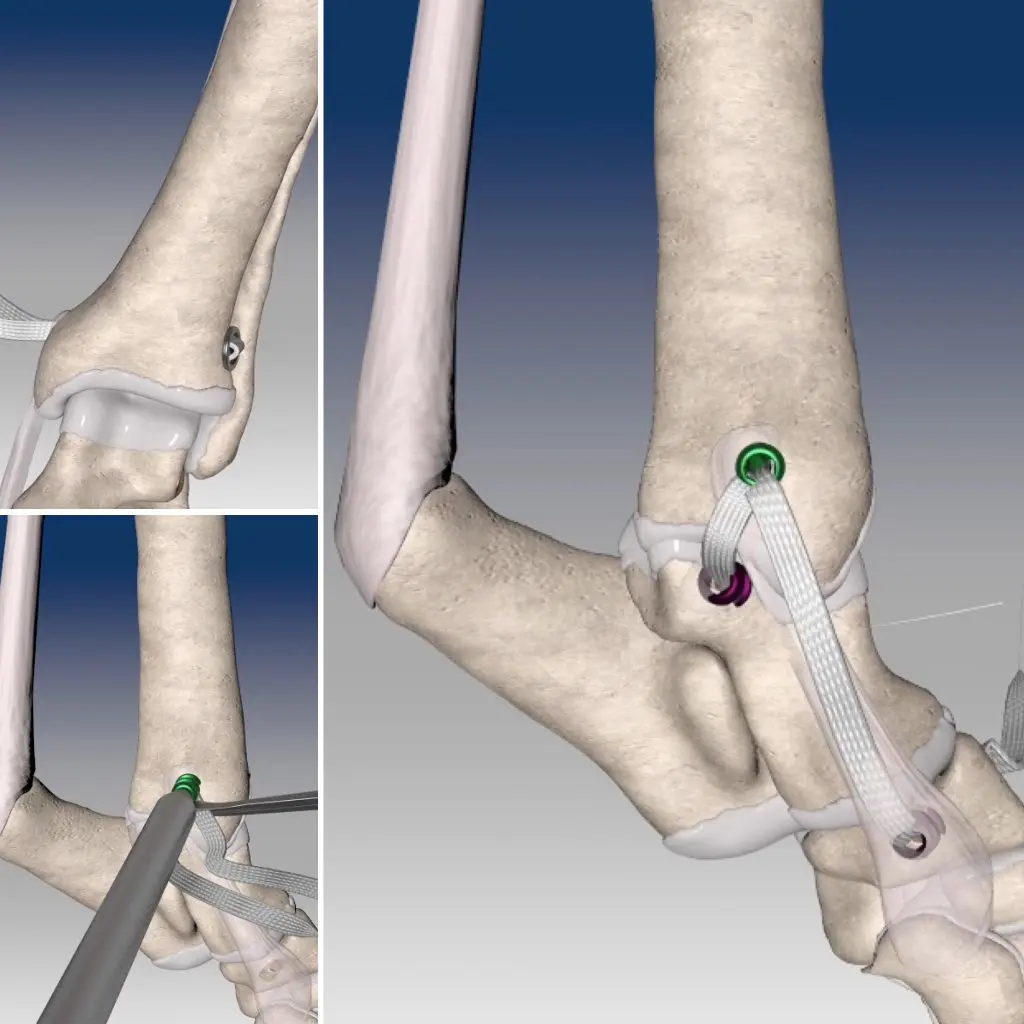

Al tratarse de una inestabilidad severa como consecuencia de una rotura completa del ligamento descrito, la alternativa terapéutica indicada es la estabilización quirúrgica de la articulación. En este sentido existen numerosas técnicas, si bien las mas vanguardistas consisten en la sustitución protésica del ligamento afectado, colocando una prótesis ligamentosa de polietileno de ultra alto peso molecular (UHMWPE).

En esta ocasión esta fue la técnica empleada. El procedimiento consiste en primer lugar en crear unos túneles óseos en la región distal de la tibia, el astrágalo y el hueso central del tarso. Seguidamente a través de éstos túneles se hacen pasar los dos cabos del ligamento protésico, siendo fijados en su lugar de inserción mediante tornillos de interferencia. Gracias a ello conseguimos reconstruir completamente tanto la banda corta como larga del ligamento afectado, recuperando la estabilidad y función articular original.